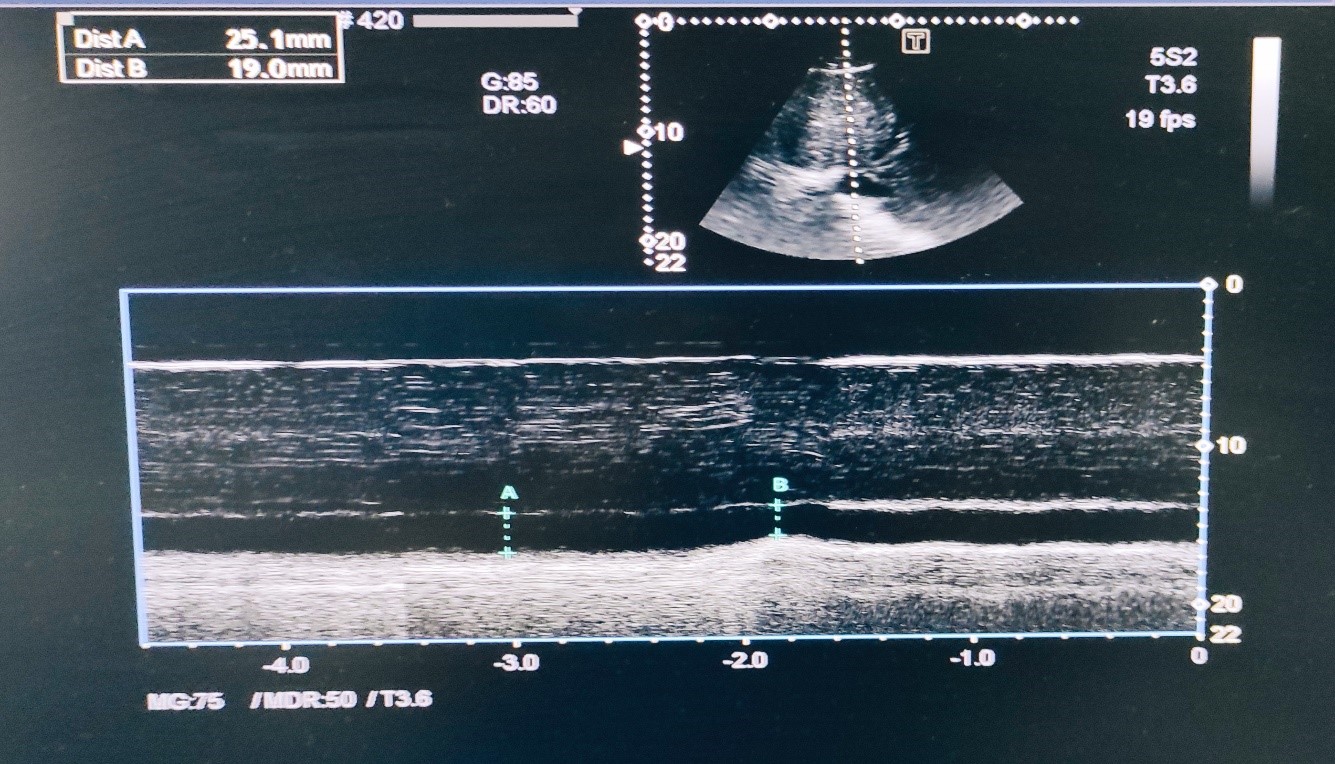

The most significant condition with a life-threatening property that must not be missed when performing POCUS, is pericardial tamponade. “The surroundings” refers to pericardium and the structures around the heart whose pathologic conditions could lead to impaired hemodynamics. Accumulation of free fluid between the two pericardial layers could be detected in all cardiac windows where pericardial effusion will be visualized as a dark anechoic area around the heart whose dimensions could vary depending on the amount of pericardial fluid [8]. In emergent cases where time to treatment is crucial, even only subcostal examination could reveal presence of pericardial effusion with or without hemodynamic compromise leading to fast treatment decision. If the anechoic dark space could be seen in all windows around the heart, then the pericardial effusion is probably big. Essential when deciding if pericardiocentesis is needed or not, is the presence or absence of hemodynamic compromise which by echocardiographic could be identified by detecting collapse of the right atrium in systole or right ventricular collapse in diastole. Right heart collapse could be identified when using subcostal or apical 4-chamber view during the examination where inward movement of the right ventricular free wall is met during diastole. Pericardial tamponade in 92% of the cases is accompanied with dilation of the IVC [8] which becomes larger than 2.5cm and non-collapsible implying impaired anterograde blood flow and should be seen and assessed in subcostal view as it was explained earlier in this article.

Figures 2 & 3. Pericardial Effusion surrounding the heart.